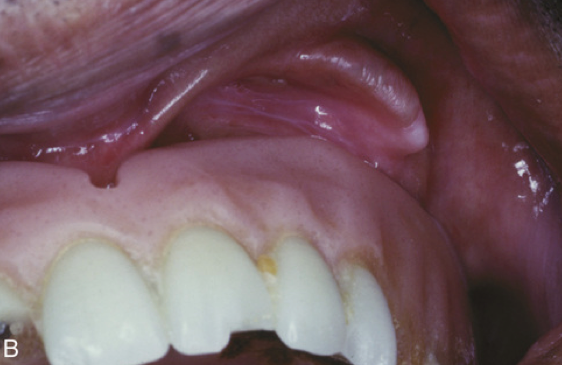

What is the likely Dx?

Epulis Fissuratum. (This is the Clinical Dx)